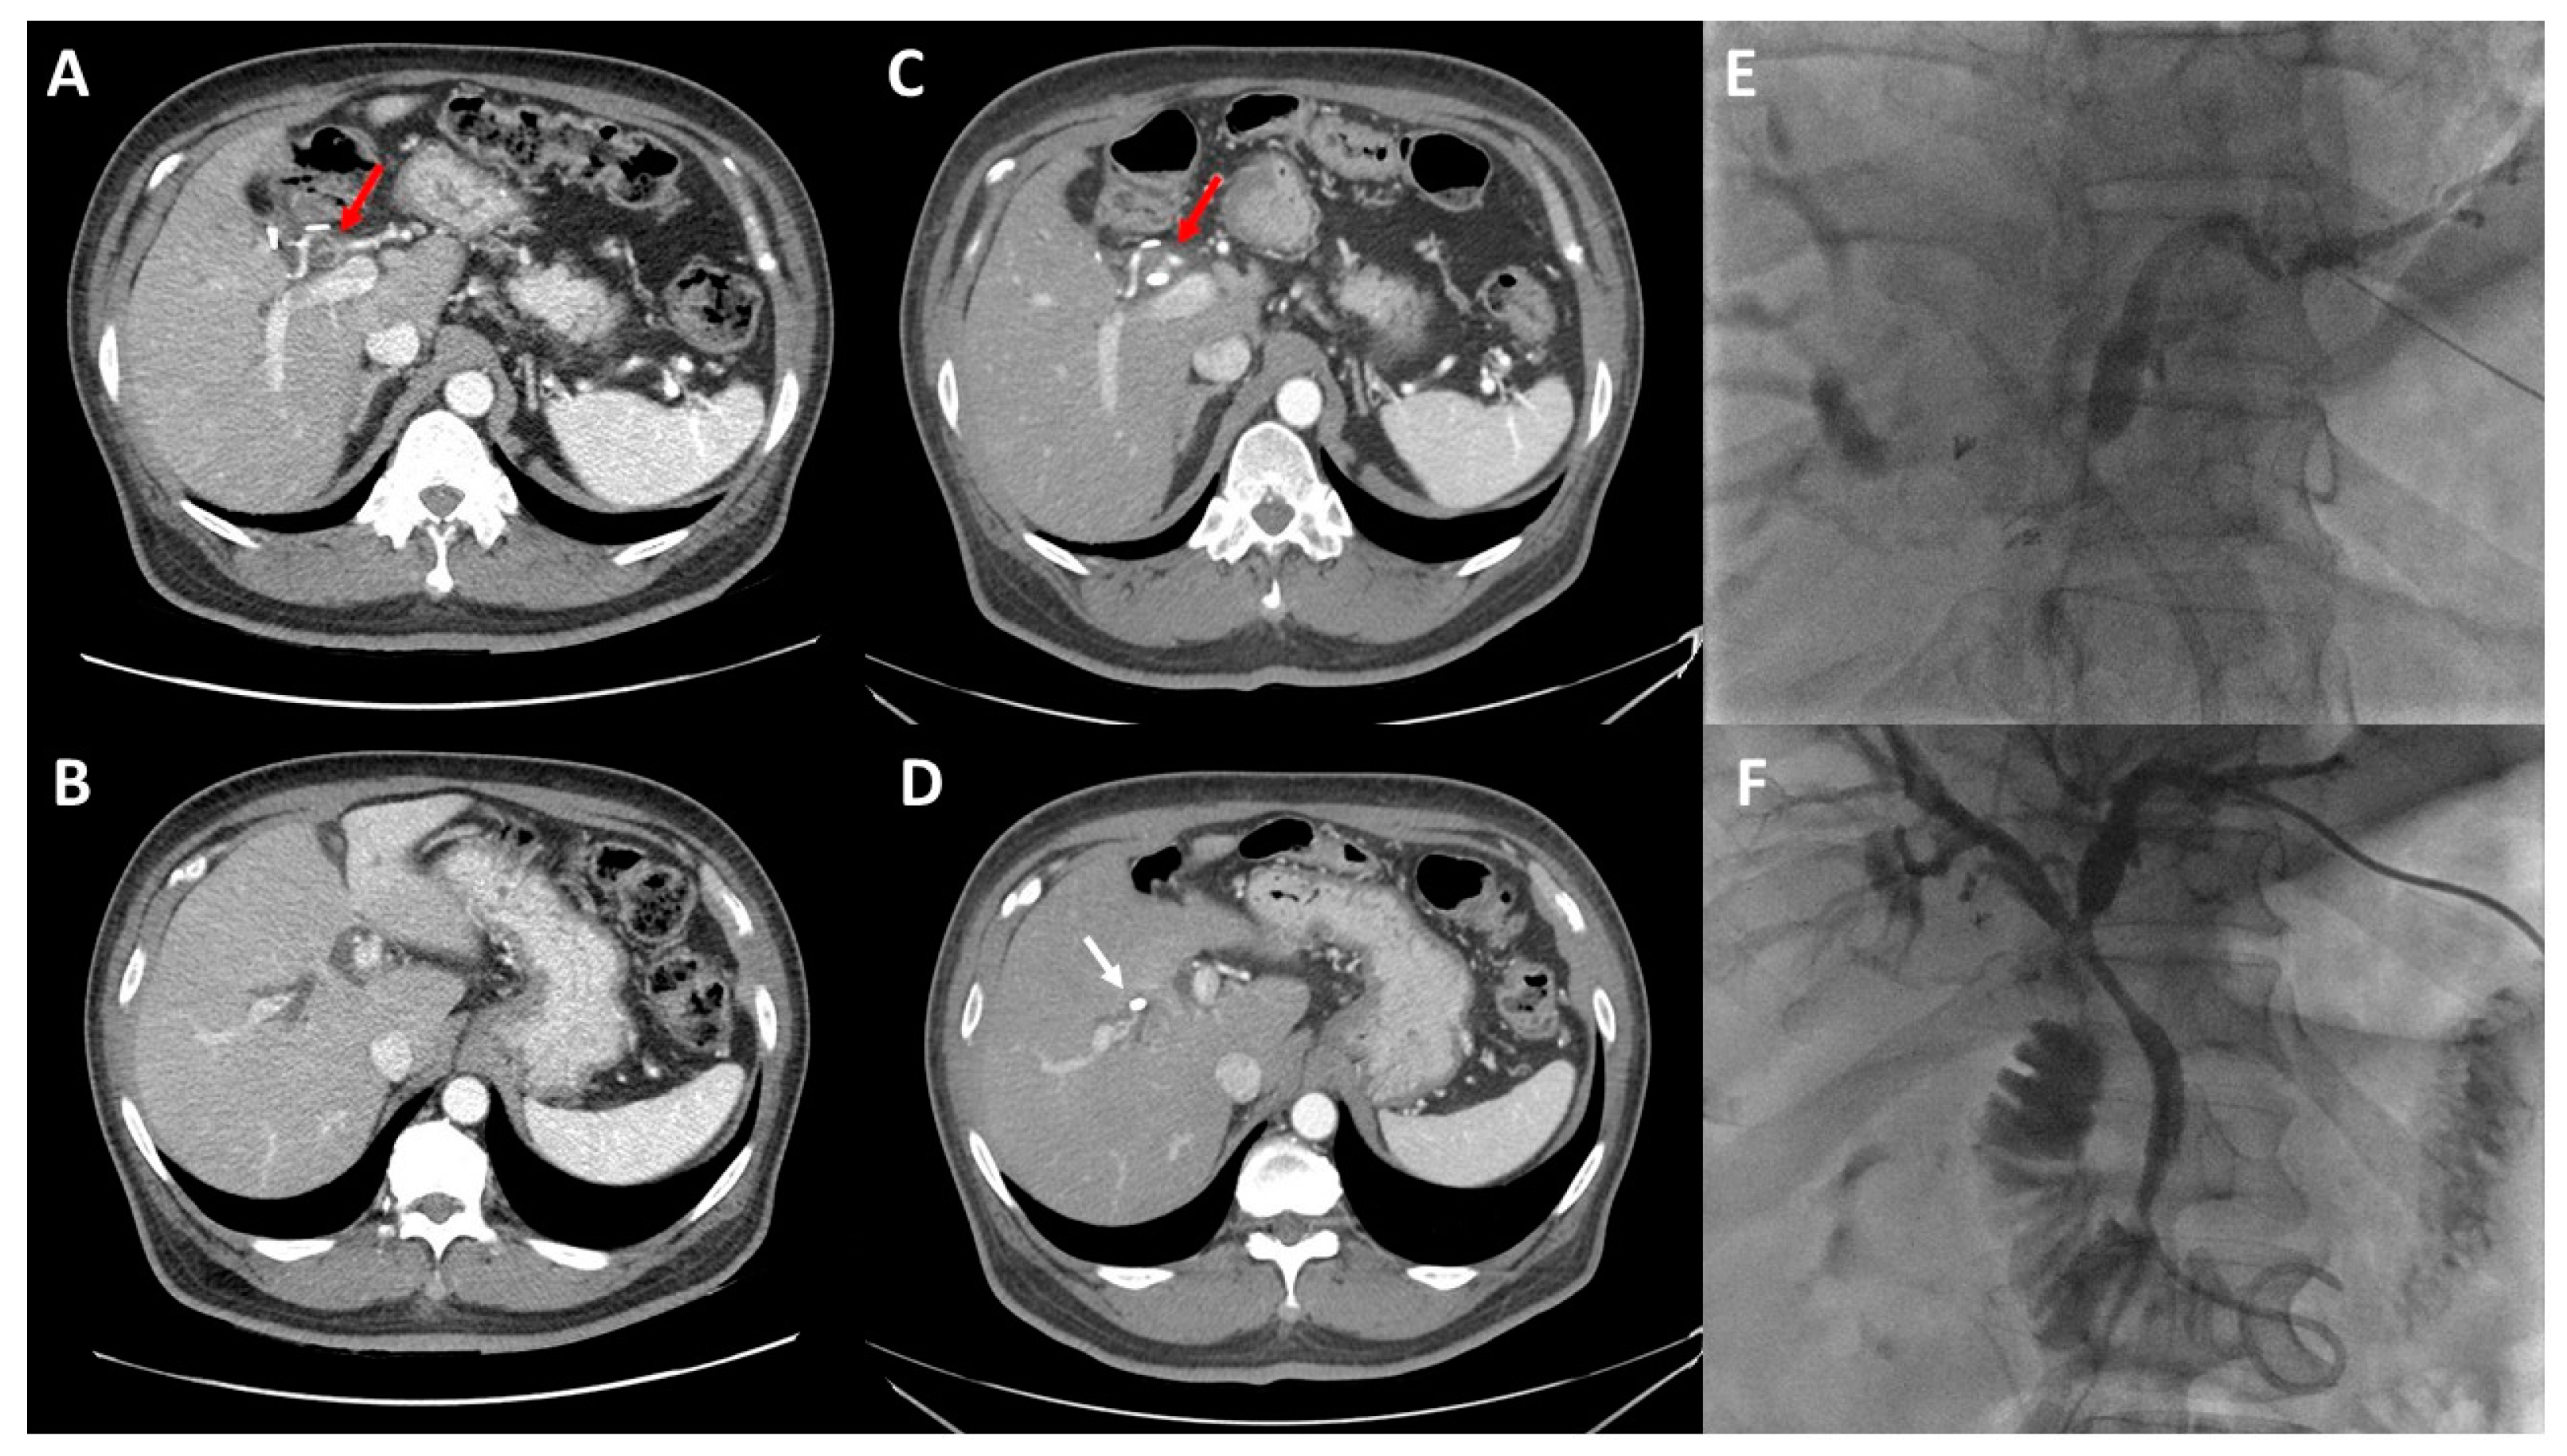

2. Preoperative Imaging